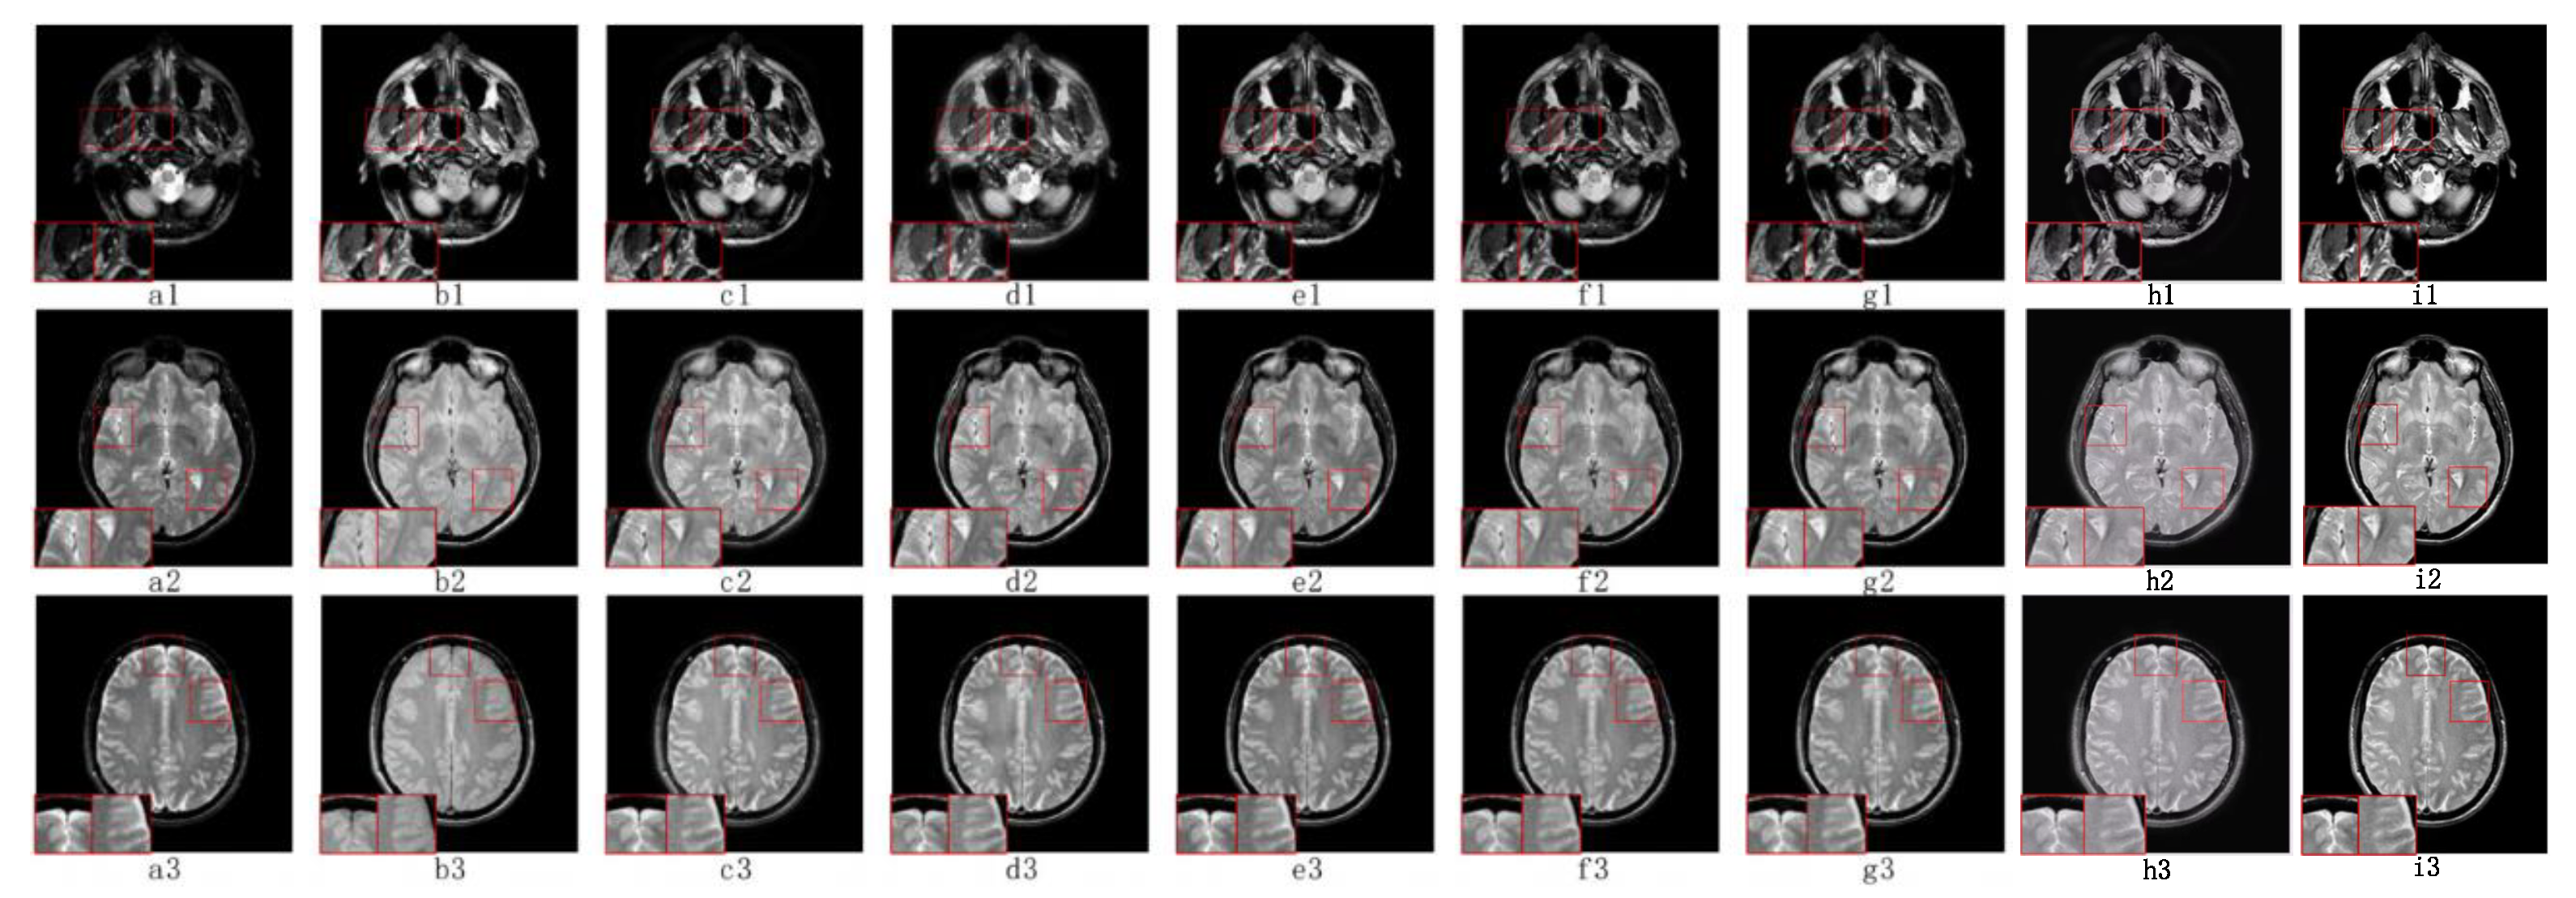

5.2. Visual Effects Analysis

5.2.3. Fusion Analysis on CT-MRI

5.2.4. Fusion Analysis on MRI-PET

5.2.5. Fusion Analysis on MR-SPECT